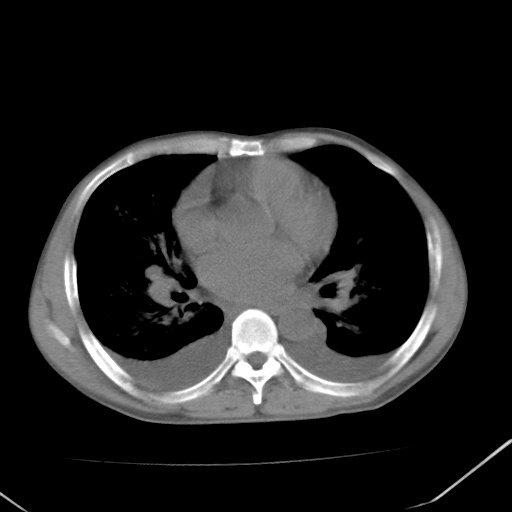

双肺野对称性磨玻璃影,分布于内中带,双侧胸水,患者有咯血。

1、间质性肺水肿;2、结合临床病史及实验室检查,考虑为肺出血肾炎综合征。    此病需与间质性炎症、粟粒性肺结核鉴别。

肺出血-肾炎综合征又称good-pasture综合征,属少见病,近几年国内有散在报告。此病原因未明,目前多数学者认为与自身免疫有关,即病人体内存在抗-gbm抗体,而病人肺毛细血管基底膜与肾小球基底膜有交叉反应性抗原,从而引起肺泡毛细血管基底膜和肾小球基底膜病变,导致肺出血及肾炎表现。血清抗-gbm抗体阳性,或组织活检见沿肾小球和肺泡基底膜有igg沉积,为本病的3个诊断依据。临床上有许多疾病同时表现为肺出血和肾炎,如系统性红斑狼疮、韦格肉芽肿和增殖性肾小球肾炎等,但这些疾病都不同时具备上述三方面的条件

双肺野广泛对称性磨玻璃影、实变影,以肺门为中心,主要分布于内中带,符合典型肺泡性肺水肿;伴双侧胸腔少量游离积液。结合患者既往病史且咯血就诊,支持多因素(尿毒症等)所致之肺水肿、肺出血、胸水;影像表现暂不考虑心源性水肿,且症状也不太符。需密切随诊结合临床治疗等进一步明确。